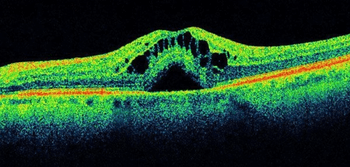

Justis P. Ehlers, MD, speaks on the key findings and take-aways from his presentation "Impact of baseline OCT characteristics on response to risuteganib for the treatment of intermediate age-related macular degeneration (AMD)."